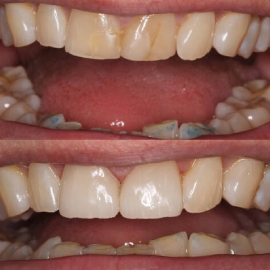

Changes in bite position with comprehensive treatment

When there is insufficient space to restore teeth

Opening the bite position provides a more stable

position also protecting the front teeth